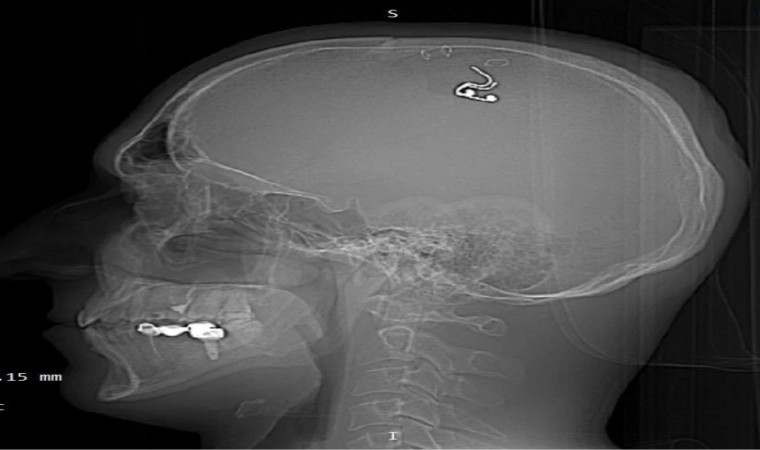

Bir süre sonra çipi kafasına yerleştirmeye karar veren Raduga, matkapla kafatasını deldi. Kan kaybetmeye başladığını fark eden Raduga, en yakın hastaneye başvurdu. Ameliyata alınan Mikhail Raduga’nın kafatasına yerleştirdiği çip çıkarılırken, hayati tehlikeyi atlattığı açıklandı.